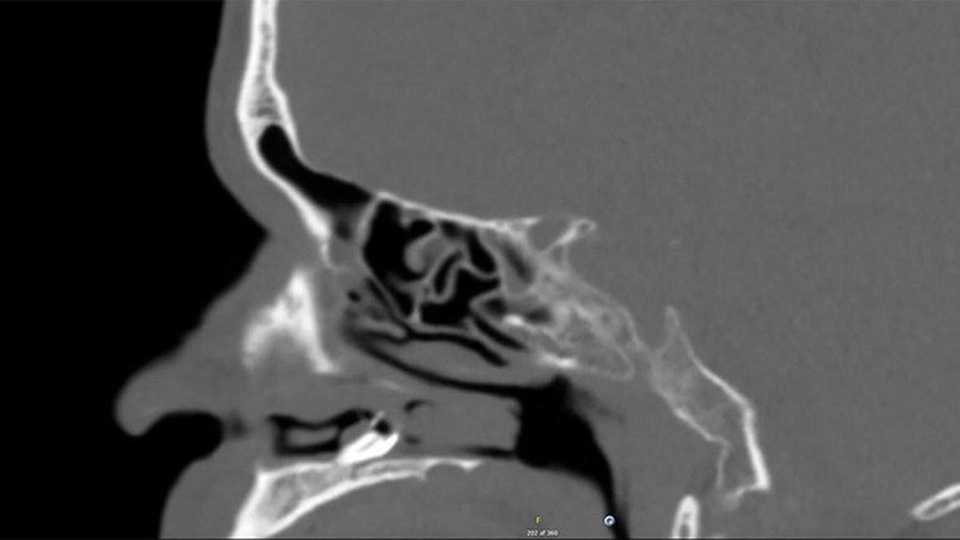

Tuy nhiên, sau khi chụp X-quang thì “danh tính” của thủ phạm chính gây ra hiện tượng trên mới được phát hiện, đó là một dị vật trắng, có lông ở khoang mũi.

Ban đầu, các bác sỹ nghi ngờ rằng đây là một khối u nang có hình dạng lạ với một số đặc điểm dị thường khác, nên đã tiến hành làm phẫu thuật cắt bỏ. Thật bất ngờ, vì sau đó họ mới nhận ra không có một khối u nào cả mà đó là một chiếc răng mọc sai chỗ.

Bác sĩ nha khoa John Hellstein cho biết, người đàn ông trên rất có thể bị mắc chứng Mesiodens ( răng thừa mọc lộn xộn). Khoảng một phần ba trong số đó có răng phát triển sai vị trí, nhưng mọc trong mũi là một trường hợp rất hiếm, chỉ chiếm 0,1-1% bệnh nhân mắc phải.